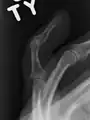

Diagnosis

The diagnosis is generally based on symptoms and supported by X-rays.[3] The injury can be accompanied by swelling and ecchymosis.[4]

X-ray showing fracture at the insertion of the extensor tendon